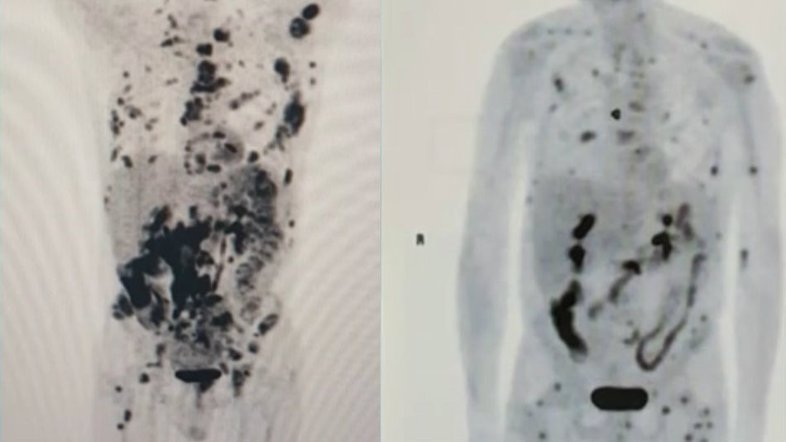

Exames feitos com pouco mais de um mês de diferença mostram o recuo de um linfoma em fase terminal em um paciente de 62 anos. Vamberto Luiz de Castro recebeu um tratamento inédito na América Latina, com uma técnica de terapia genética descoberta no exterior e conhecida como CART-Cell. As informações são do G1.

No início de setembro, segundo a publicação, o corpo do mineiro estava tomado por tumores, mas, nesta semana, a maioria já desapareceu. Segundo os médicos, isso é um indicativo da evolução da terapia. Para pesquisadores do Centro de Terapia Celular (CTC-Fapesp-USP), ligado ao Hospital das Clínicas de Ribeirão Preto, Vamberto está praticamente livre da doença.